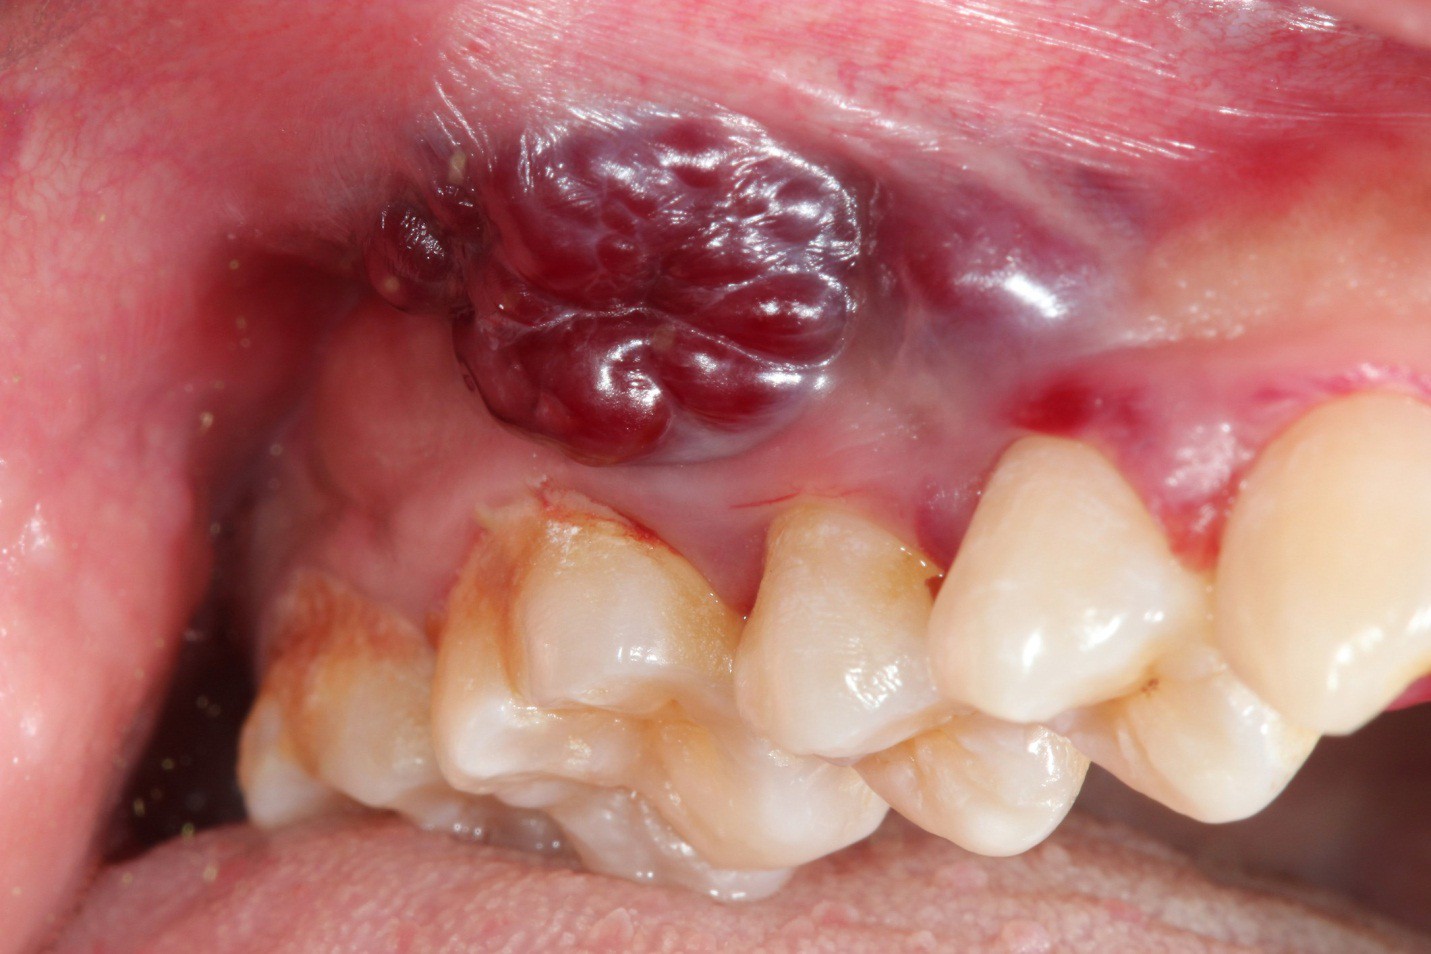

Ảnh minh họa. Nguồn: decisionsindentistry.com

Biểu hiện sớm của ung thư miệng và họng là một hoặc nhiều thay đổi mô mềm trong miệng về hình ảnh và cảm giác. Những dấu hiệu và triệu chứng có thể gồm:

- Những khối hoặc mảng trắng, đỏ hoặc đen bên trong miệng;

- Những mảng đỏ trong miệng (hồng sản). Hồng sản có nhiều khả năng phát triển thành ung thư hơn bạch sản. Hầu hết những trường hợp này cuối cùng được chẩn đoán là ung thư. Những vùng này thường dễ chảy máu khi chà xát.